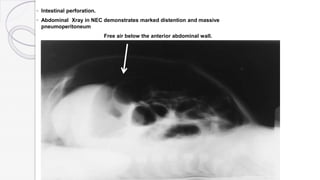

◦ Intestinal perforation.

◦ Abdominal Xray in NEC demonstrates marked distention and massive

pneumoperitoneum

Free air below the anterior abdominal wall.